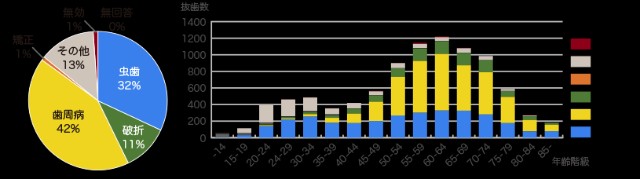

そうして、歯を支えている骨がなくなってしまうと

ぐらぐらしてきて

歯が抜けてしまいます

これが歯がなくなってしまう原因の

第一位です!!